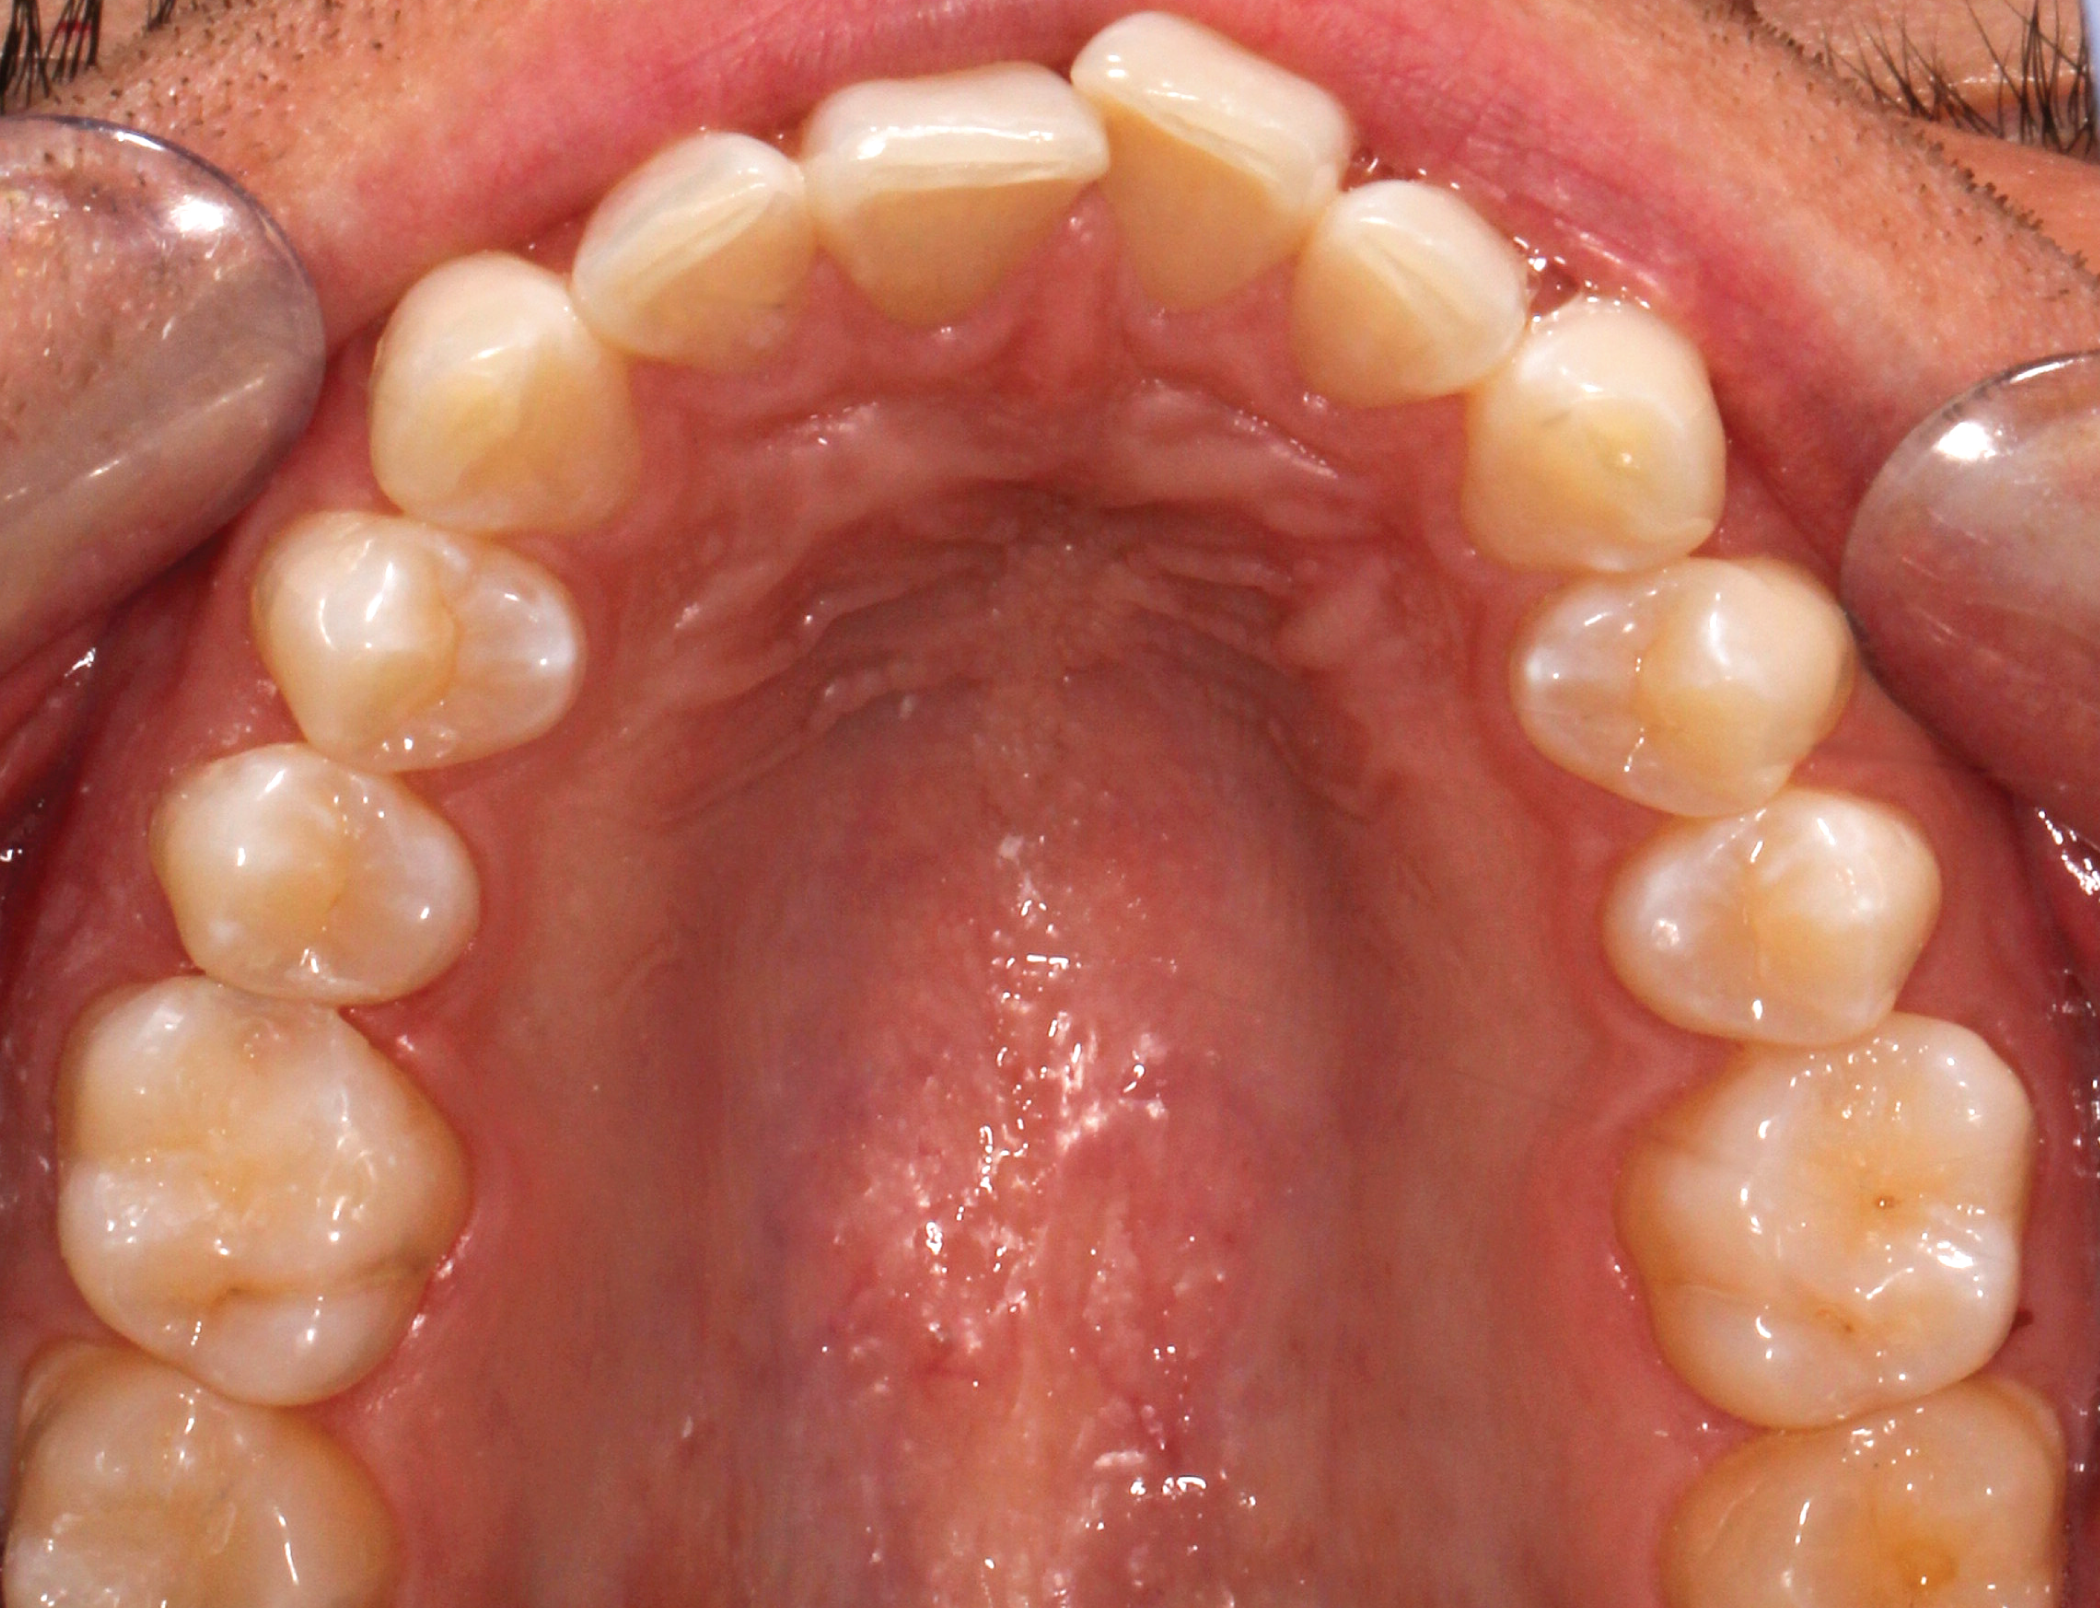

The treatment goals for clear aligner therapy were focused on rotating tooth 9, extruding tooth 9 and subsequent enameloplasty to even out the maxillary anterior teeth. The patient also had mild Class II molar and canine relationships with crowding and spacing discrepancies in the anterior teeth. The goal with the extrusion of tooth 9 was to move the adjacent bone and soft tissue coronal with the tooth movement. Additional space was needed for the maxillary teeth to accommodate the rotation of tooth 9 into the correct position. Lastly, extra spacing between the lower teeth was to be treated along with the mild Class II malocclusion (Figs. 1-8).

Fig. 5: Pre-op (upper occlusal view) Fig. 6: Pre-op (lower occlusal view)